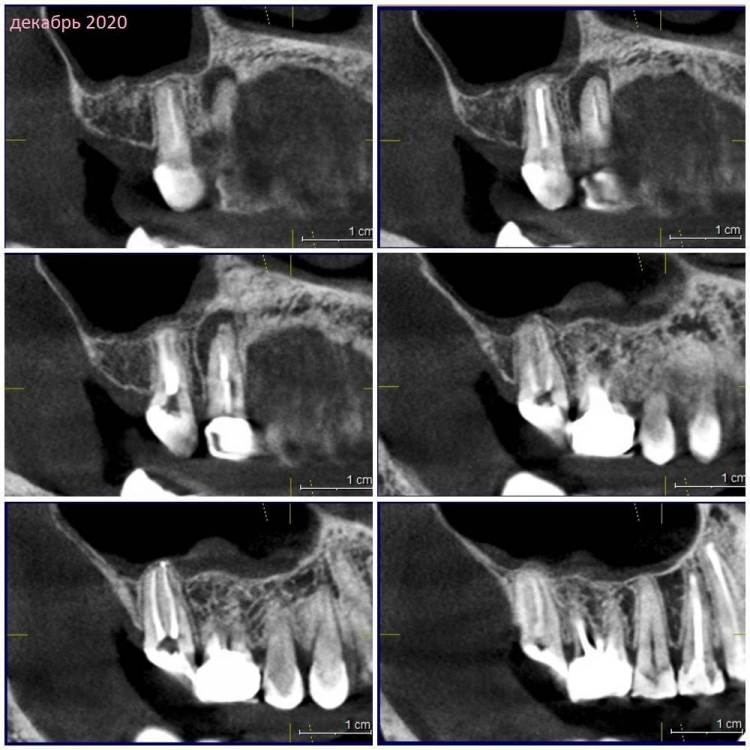

Зуб 17.

КТ наскринила парочку. Если нужно будет более подробно – выложу еще.

Декабрь 2020